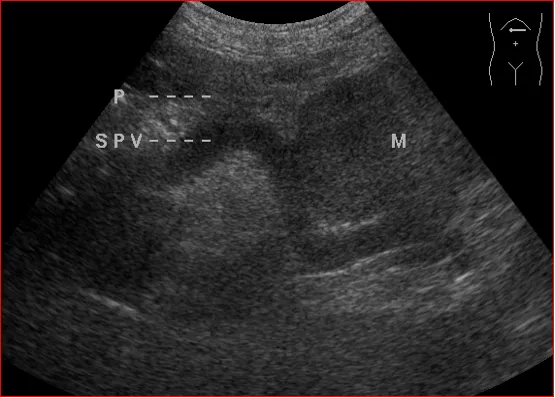

上腹部斜纵切显示胰头癌压迫胆总管

上腹部横切显示胰体部占位与腹腔干的关系

上腹部横切显示胰尾部占位压迫脾静脉呈“Z”形

饮水后上腹部横切,显示胰尾部占位与胃体后壁的关系